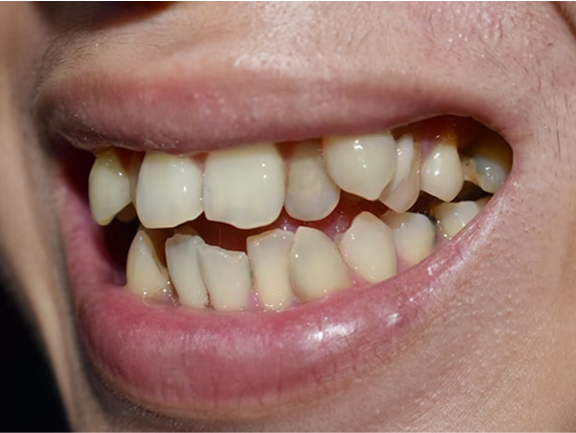

Underbite

The child’s upper jaw is narrower than the lower jaw, resulting in the back top teeth biting inside the back bottom teeth.

Crossbite

Using X-rays and our years of experience helping Atlanta kids enjoy beautiful, straight smiles, we can tell ahead of time that your child’s mouth isn’t large enough to accommodate all their incoming adult teeth. Widening the upper jaw can create the space needed for a straight smile without extractions.